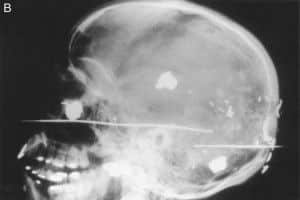

(B) lateral

Vista muestra la inutilidad de sondeo para las balas.